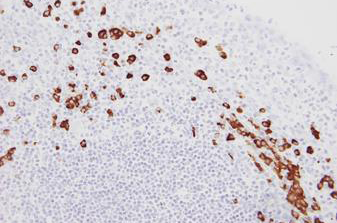

Human tonsil: in situ hybridization for kappa mRNA using Kappa Probe, Anti-Fluorescein Antibody and BOND Polymer Refine Detection.

Kappa Probe is used for the qualitative identification of Kappa light chain messenger RNA (mRNA) in formalin-fixed, paraffin-embedded tissue by in situ hybridization (ISH) using the automated BOND system.

Kappa Probe is used in conjunction with Lambda Probe for the detection of antibody producing B-cells in formalin-fixed, paraffin embedded tissue.